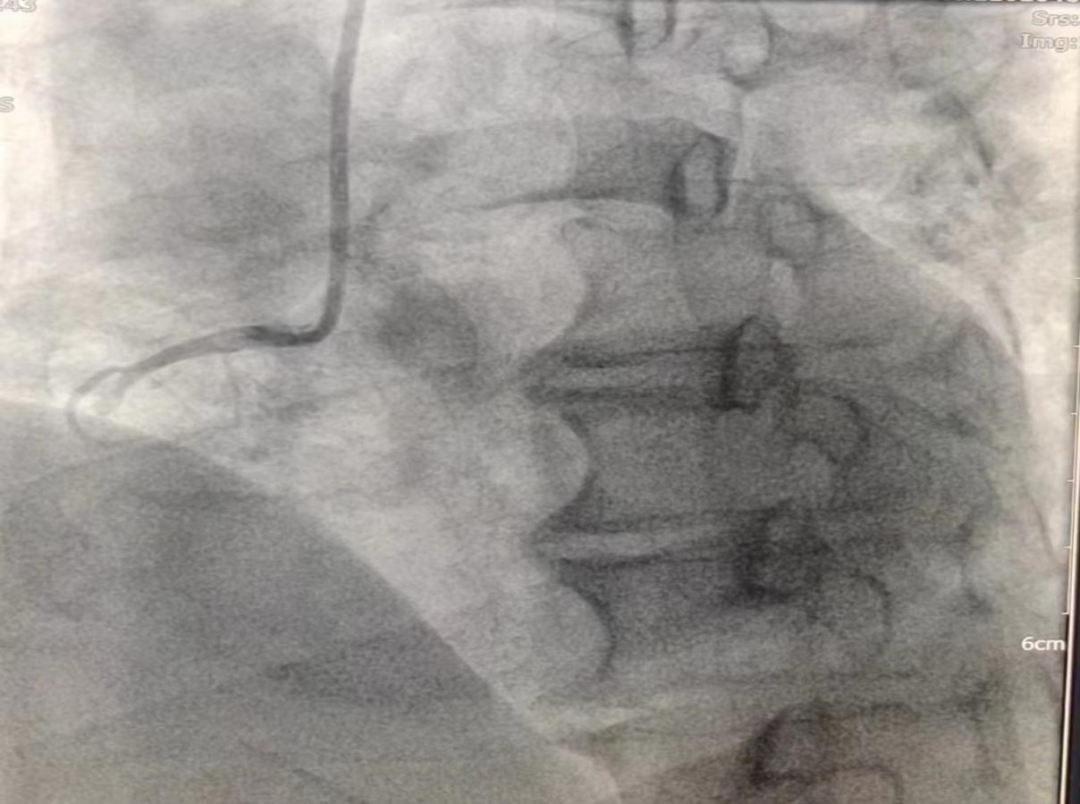

女性患者,49歲,突發暈厥急診我院,經診斷為:冠狀動脈粥樣硬化性心臟病、2型糖尿病。導入造影導管行冠狀動脈造影示:冠狀動脈分布呈左冠優勢型,LM未見明顯狹窄,血流TIMI3級;LAD全程多發斑塊,中段狹窄約60%,遠端狹窄約50%,D1未見明顯狹窄,血流TIMI3級;LCX未見明顯狹窄,血流TIMI3級,RCA近端狹窄約50%,中段發出圓錐支后完全閉塞,血流TIMI0級,急診開通血管并充分擴張,殘余狹窄仍然嚴重。在與患者及家屬溝通時,其了解得知臨床有一種新型的可吸收支架,植入體內后支架能完全被降解和吸收,希望能用這種新型的支架進行手術治療。由于生物可吸收支架有著嚴格的適應癥,因此經過嚴格篩選評估,最終對患者進行了Xinsorb生物可吸收支架置入術。支架植入術前經過充分預擴張,按照規范的可吸收支架操作流程,快速送入可吸收支架到病變部位,精準定位后14個大氣壓釋放,生物可吸收支架后擴球囊擴張。充分球囊后擴張,以保證支架貼壁良好,血流速度正常,造影完美,手術順利結束。

(圖為右冠病變術前影像)